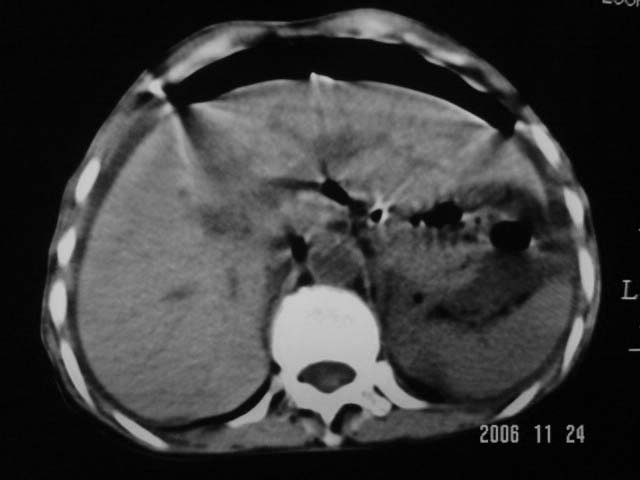

仰卧位见:肝前间隙及肝脾间隙内可见新月形气体密度影,边缘清楚,侧卧位见气体随体位改变而移动,ct值约-929hu。膈下、肝下间隙及部分肠间隙可见液性密度影。考虑:1、上腹部空腔脏器穿孔,以胃穿孔可能性大。2、少量腹水。

仰卧位见:肝前间隙及肝脾间隙内可见新月形气体密度影,边缘清楚,侧卧位见气体随体位改变而移动,ct值约-929hu。膈下、肝下间隙及部分肠间隙可见液性密度影。考虑:1、上腹部空腔脏器穿孔,结合临床,首先考虑胃穿孔可能性大。2、少量腹水

支持消化道空腔脏器穿孔(腹腔内大量游离气体影,小网膜囊内亦见气体影),少量腹水。